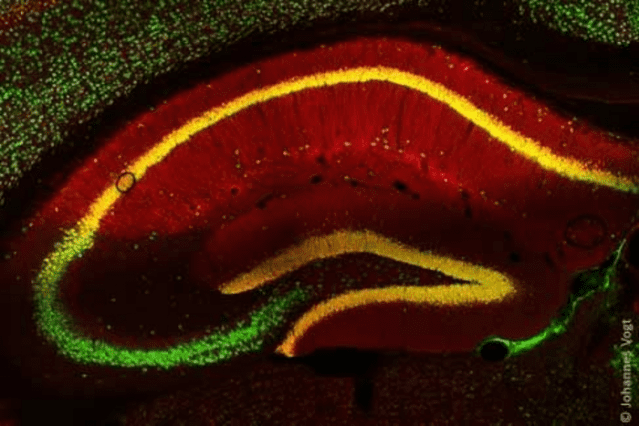

과식을 유발하는 뇌 내 신경세포의 작동 과정이 규명됐다. 과식이나 비만 방지를 위한 신약 개발의 실마리가 되리란 기대다.

독일 쾰른대학교 연구진은 뇌 시상하부에 있는 '아구티 연관 펩타이드 뉴런(AgRP, agouti-related peptide neurons)'이 리소인지질산(LPA)의 분비를 조절하고, LPA가 다시 대뇌피질의 신경세포를 조절, 공복감을 느끼게 해 음식을 먹도록 자극함을 발견했다.

이 과정에서 LPA를 만드는 오토탁신이란 효소가 신호 경로 조절의 핵심 역할을 하는 것으로 나타났다. AgRP가 혈액 안 리소포스파티딜콜린(LPC, lysophosphatidylcholine)이란 물질의 양을 조절하고, 뇌에 전달된 LPC는 오토탁신에 의해 LPA로 바뀌어 시냅스에서 활성화된다.

연구팀은 혈액 속 LPC 증가가 뇌의 LPA 자극으로 이어져 음식을 찾게 만드는 이같은 과정을 모델 쥐에서 확인됐다. 오토탁신을 억제한 모델 쥐는 공복 후에도 음식 섭취가 늘지 않았다. 오토탁신 억제 처치를 지속적으로 받은 비만 쥐는 몸무게가 줄었다. 또 LPA 신호 기능에 이상이 있는 사람은 비만과 이형당뇨병이 나타날 확률이 크다는 점도 발견했다.